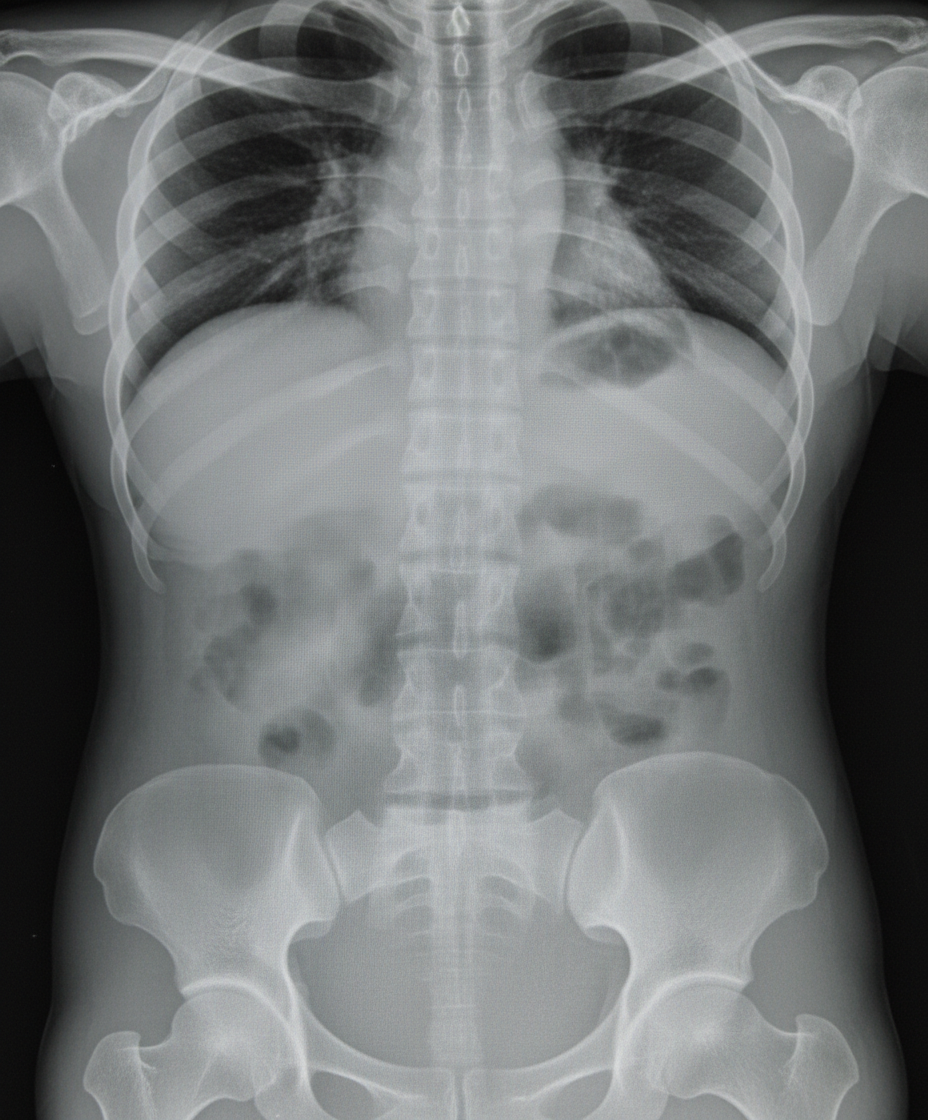

A patient presents with complaints of fever and abdominal distention. He is having history of bloody diarrhea off and on for previous 6 months. X-ray abdomen is shown below. What is the diagnosis?

Explanation: ***Toxic megacolon*** - The image shows **marked dilation of the colon** with loss of haustral markings, consistent with megacolon. - The clinical picture of fever, abdominal distention, and bloody diarrhea in a patient with a history of inflammatory bowel disease (implied by chronic bloody diarrhea) strongly suggests **toxic megacolon**. - Toxic megacolon is a life-threatening complication of IBD requiring urgent management. *Pneumatosis intestinalis* - This condition involves **gas within the wall of the bowel**, which would appear as characteristic lucencies outlining the bowel wall on X-ray. - While it can be seen in severe bowel ischemia, it is not the primary finding of diffuse colonic dilation seen here. *Volvulus* - Volvulus is a **twisting of a loop of intestine** around its mesentery, leading to obstruction and ischemia. - While it can cause colonic dilation, the dilation is typically localized to the twisted segment (e.g., a "coffee bean" sign in sigmoid volvulus) rather than the diffuse involvement seen here. *Intestinal perforation* - Intestinal perforation is characterized by the presence of **free air under the diaphragm** (pneumoperitoneum) on an upright chest X-ray or lateral decubitus abdominal film. - While a severely dilated and inflamed colon can perforate, there is no clear evidence of free air outside the bowel wall in this X-ray. *Paralytic ileus* - Paralytic ileus causes **generalized bowel dilation** and can present with abdominal distention. - However, it typically involves both small and large bowel, lacks the **loss of haustral markings** specific to toxic megacolon, and does not typically present with **fever and bloody diarrhea** in the context of chronic inflammatory bowel disease.